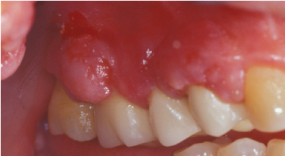

Ορατό εξόγκωμα στα ούλα κοντά σε ένα δόντι

Όσο συγκεντρώνεται περισσότερο πύο, η πίεση αυξάνεται και το απόστημα γίνεται όλο και πιο επώδυνο. Μερικές φορές το πύον μπορεί να βρει δίοδο παροχέτευσης στο στόμα είτε μέσω των περιοδοντικών θυλάκων και της ουλοδοντικής σχισμής είτε μέσω της δημιουργίας συριγγίου.